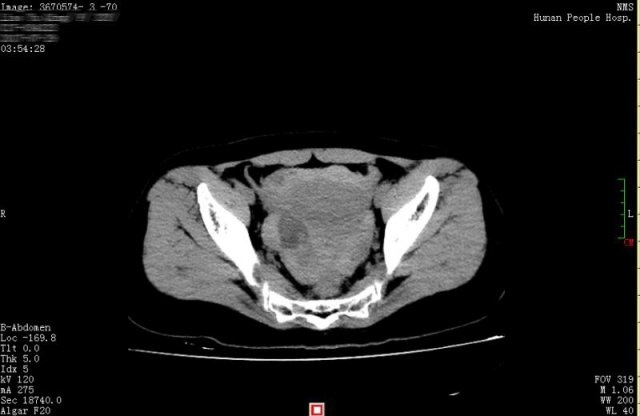

| Bản chụp CT phát hiện ra rằng Hiểu Khánh có một lượng máu lớn và chất lỏng trong ổ bụng và vùng chậu. Ảnh: Xiaoxiang Morning Post. |

Bác sĩ Huang Mei thuộc Bệnh viện Nhân dân tỉnh Hồ Nam (Trung Quốc) cho biết Hiểu Khánh không mang thai, bản chụp CT phát hiện ra cô có một lượng máu lớn và chất lỏng trong ổ bụng và vùng chậu.